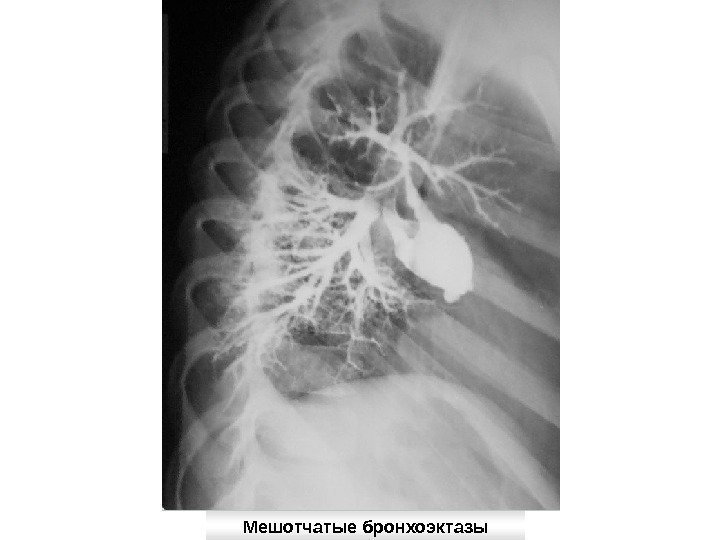

Бронхоэктатическая болезнь — это регионарное расширение бронхов (бронхоэктазы), возникающее в детстве и проявляющееся хроническим, преимущественно эндобронхиальным нагноением. Классификация бронхоэктазов: Первичные (врожденные) и вторичные (на фоне заболеваний бронхолегочной системы) Одиночные и множественные По форме расширения бронхов: цилиндрические, мешотчатые, веретенообразные, смешанные бронхоэктазы По стороне поражения: односторонние и двусторонние.

Рентгенологически определяется повышение прозрачности легочной ткани, усиление легочного рисунка, характерная ячеистость. При перкуссии специфичные признаки не обнаруживаются При аускультации имеет значение аускультация над областью бронхоэктазов, будут выслушиваться стойко удерживающиеся очаги влажных, среднепузырчатых хрипов, иногда — сухие хрипы Основной метод диагностики — бронхография

Мешотчатые бронхоэктазы